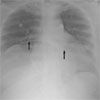

A CT scan confirmed the displacement of the entire stomach into the chest; the lung parenchyma was considerably displaced by the herniation. The shape of the gastric contour is clearly visible on the right side of the chest, and a gastric air-fluid level is present (B, arrow).

Figure 2